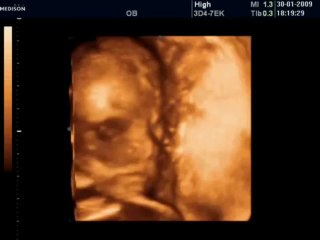

BCF Ultrason Görüntüsü - Hasvet Medikal